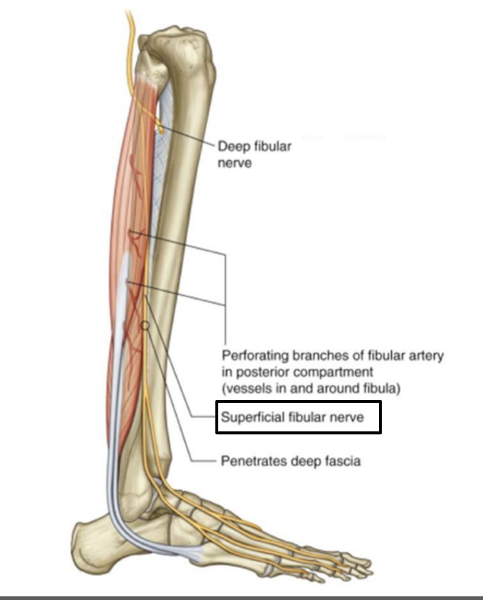

The superficial fibular nerve is the (lateral/medial) branch of the ________

lateral; common fibular nerve

which muscles does the superficial fibular nerve innervate?

both lateral leg muscles (fibularis longus and fibularis brevis)

The deep fibular nerve is the (medial/lateral) division of the _________-

medial; common fibular nerve

What is the path of the deep fibular nerve?

travels between tibialis anterior and extensor hallucis longus

continues onto the dorsum of the foot for sensory innervation in the flip flop area

What is the pathway of the superficial fibular nerve?

runs between fibularis longus and fibularis brevis

continues onto the dorsum of the foot

Which muscles does the deep fibular nerve innervate?

innervates all anterior leg muscles (extensor hallucis longus, extensor digitorum longus, tibialis anterior, and fibularis tertius) and both muscles of the dorsum of the foot (extensor digitorum brevis, extensor hallucis brevis)

OCD of superficial fibular nerve

O common fibular nerve

C arises between fibularis longus and neck of fibula. descends into lateral compartment of leg; pierces deep fascia at distal third of leg to become subcutaneous

D fibularis longus and brevis. medial dorsal cutaneous n, intermediate dorsal cutaneous n

OCD of deep fibular nerve

O common fibular nerve

C arises between fibularis longus and neck of fibula; passes through extensor digitorum longus and descends on interosseous membrane. crosses distal end of tibia and enters dorsum of foot.

D tibialis anterior, extensors digitorum brevis and longus, extensor hallucis brevis and longus, and fibularis tertius. lateral cutaneous of big toes, medial cutaneous of second toe.